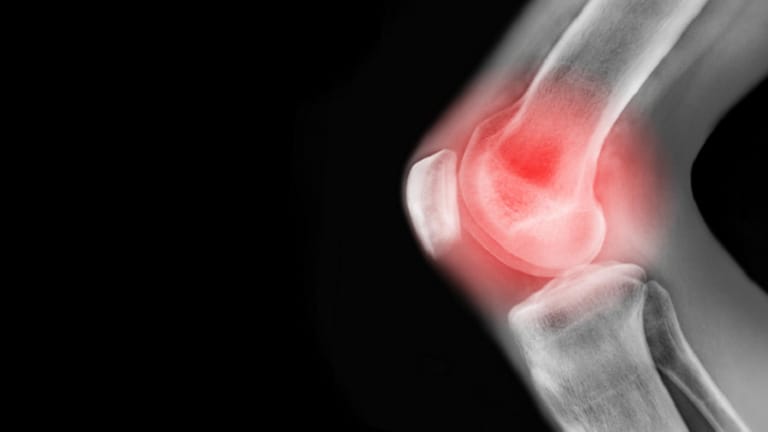

علاجٌ غير دوائي لألم الركبة

أثبتت دراسة حديثة أن تعديل طريقة المشي يمكن أن يقلل آلام هشاشة العظام ويؤخّر الحاجة لجراحة الركبة لسنوات، ما يفتح الباب أمام علاج غير دوائي لهذه الحالة الشائعة.

وتُعرف هشاشة العظام بأنها مرض تنكسي يؤدي إلى تآكل الغضاريف التي تبطن أطراف العظام، ما يسبب الألم والتصلب وضعف الحركة. وحتى الآن، يقتصر العلاج على تخفيف الألم بالأدوية، وفي مراحل متقدمة، استبدال المفصل جراحيا.